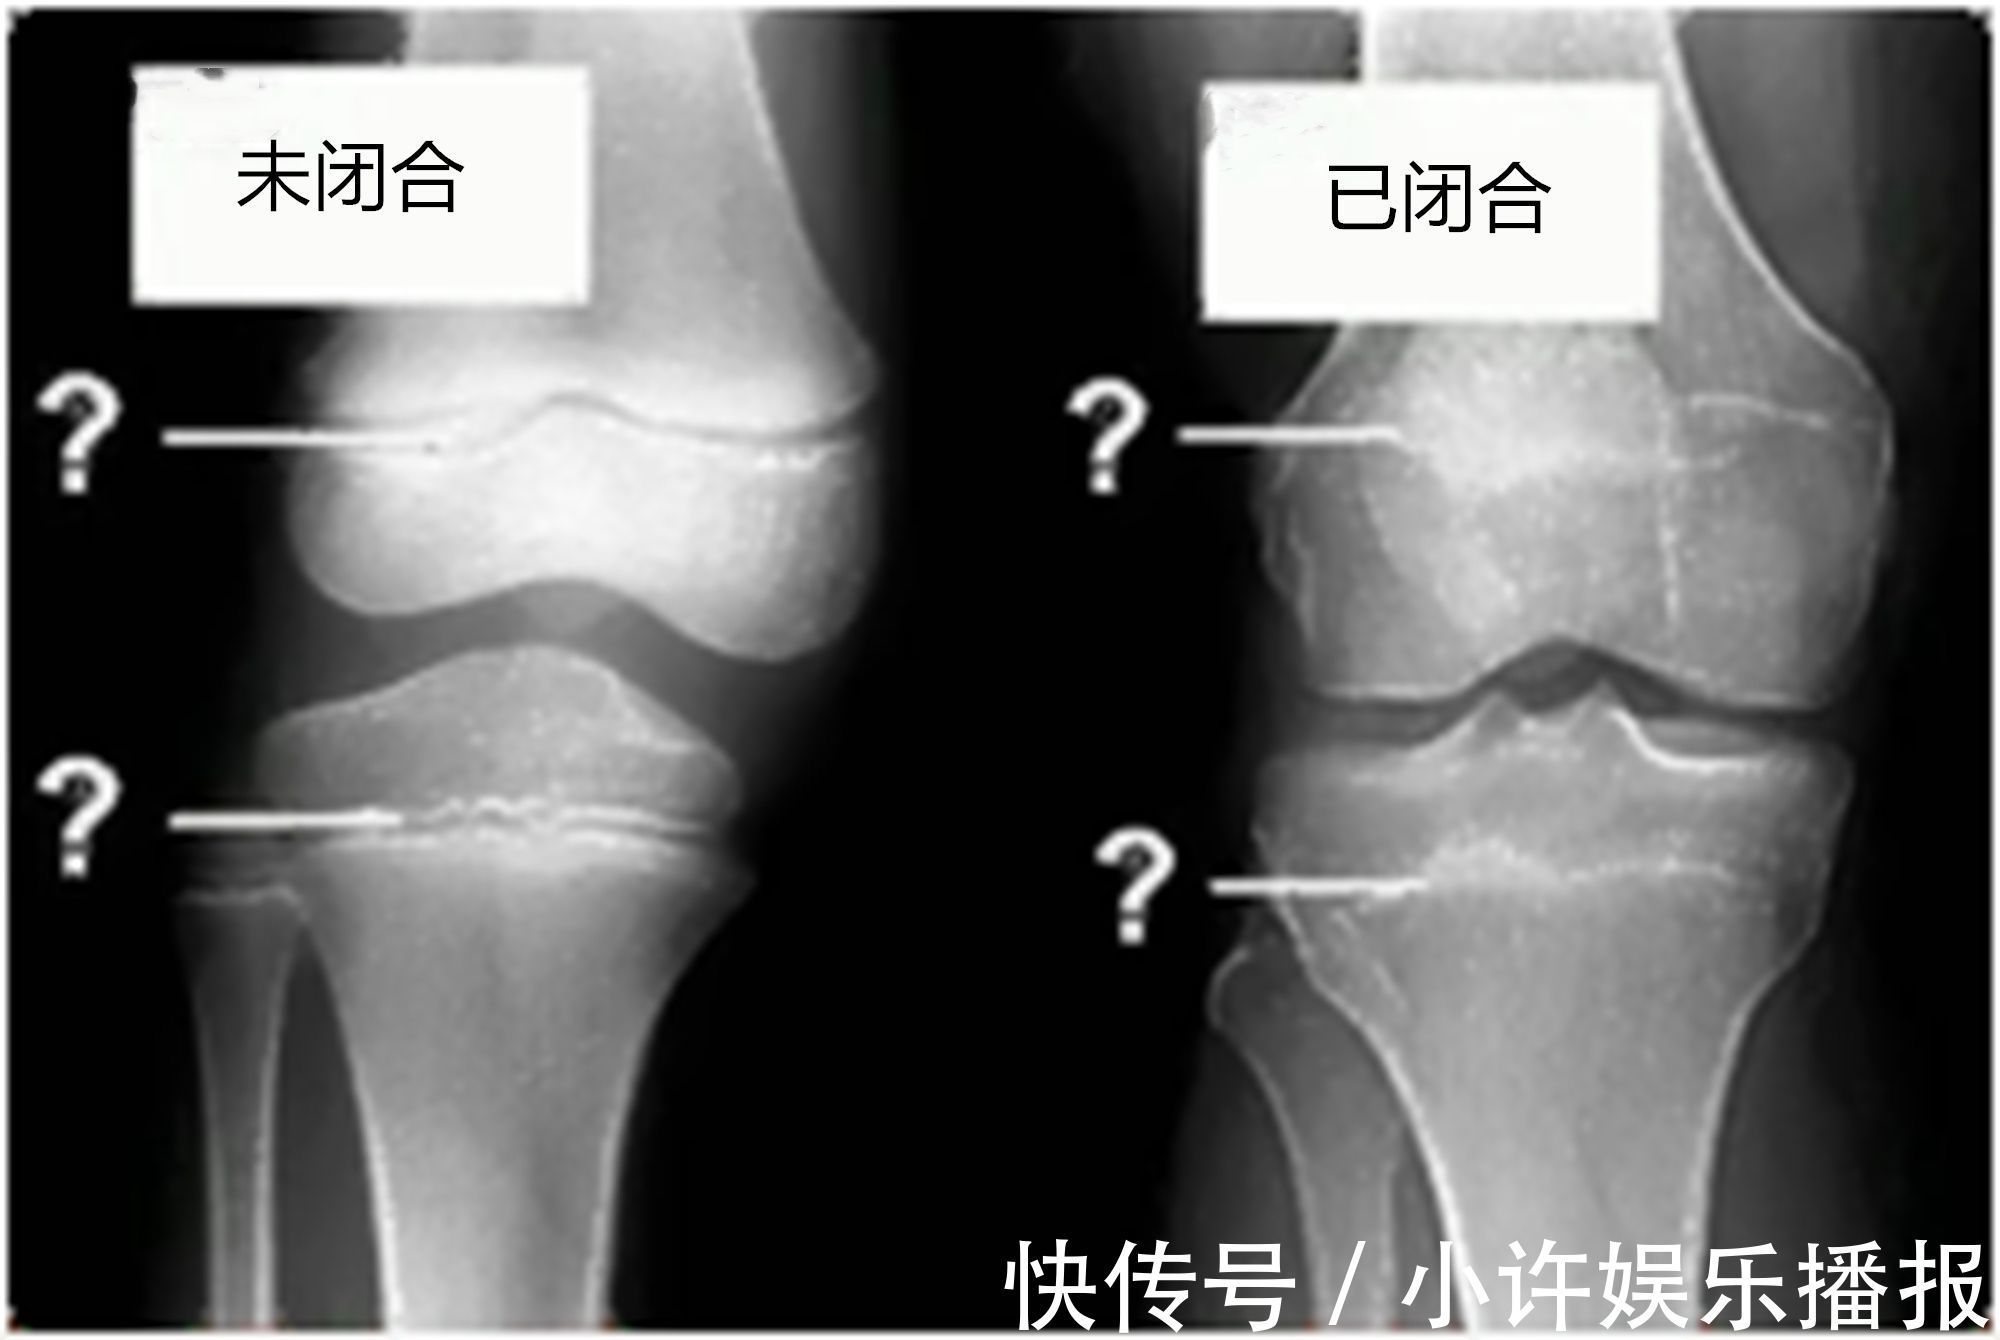

骨骼线是什么?它是怎样影响身高的呢??骨骼线的其实是一种软骨,直白来说它位于两根骨骼之间,它有一点极为特殊,也就是它会随着年龄的增长逐渐缩短并骨化。

当软骨完全骨化后,就形成一条紧密的缝,此时骨骼线完全闭合,也就意味着骨骼停止生长,就真的很难再长高了。